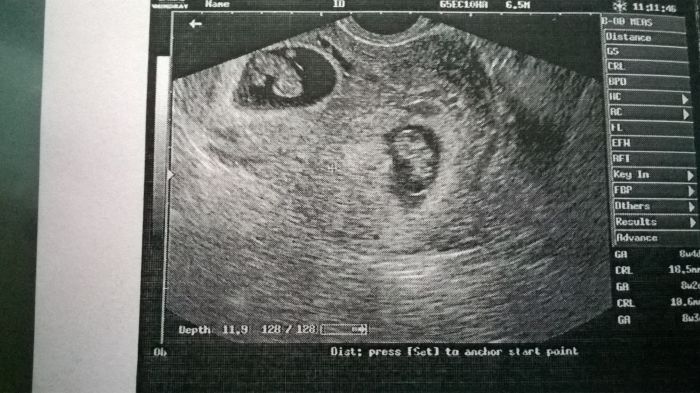

Autor: Bluumy 24.4.2017 v 21:02

Holky prace ze nemame :D jsou dvojvajecna, kazdej ma svy vsechno a tedka jsem v 10 tydnu, za tri tydny na kontrolu, uz se na ne tesim :D

[992807] Ty jo, tak to je dokonalá fotka, nádherná, nikdy jsem s dvojčátkama neviděla:-)tak to může být páreček...ty máš chlapečka, že? Necháte si říct pohlaví?

[992807] JUUU TO JE KRASNY :-) přeju hodne zdravíčka a at ti miminka krasne rostou :-)